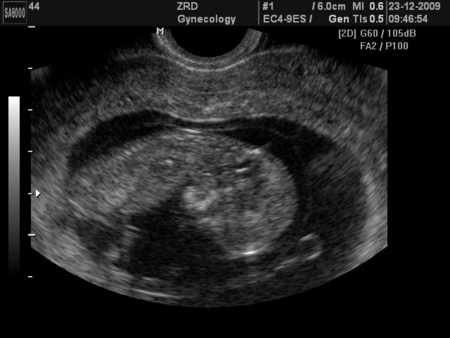

Послала меня на кресло, пощупала, киста пока так и осталась, блин, как слева нажала, я чуть не опписалась(( так больно, а она грит, до 16 недель еще будет, потом должна пройти. Мазочек взяла на всякий случай, я сама попросила для успокоения. С кресла слезла, а Г молчит как партизан, я говорю Ну что ТАМ? все впорядке? она улыбается и говорит РАСТЕМ)))) я обрадовалась, думаю, слава Богу, переживала уж сильно. Больше на кресле смотреть не будет...толко если что-то экстренное...